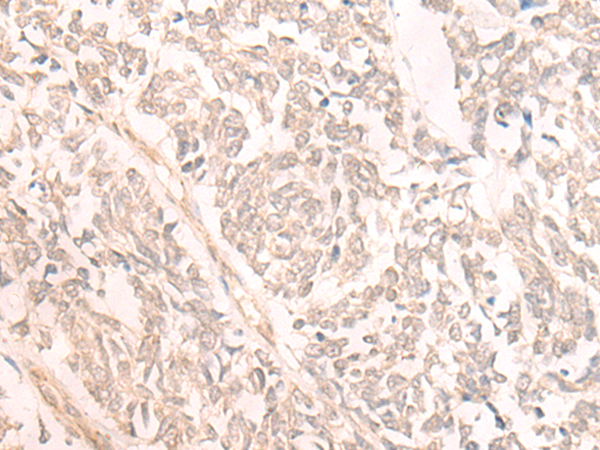

IHC positive control: |

Human lung cancer |

IHC Recommend dilution: |

30-150 |